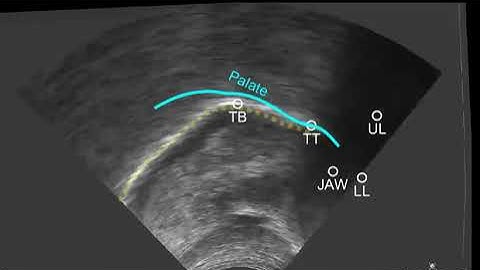

SottoVoce: An Ultrasound Imaging-Based Silent Speech Interaction Using Deep Neural Networks